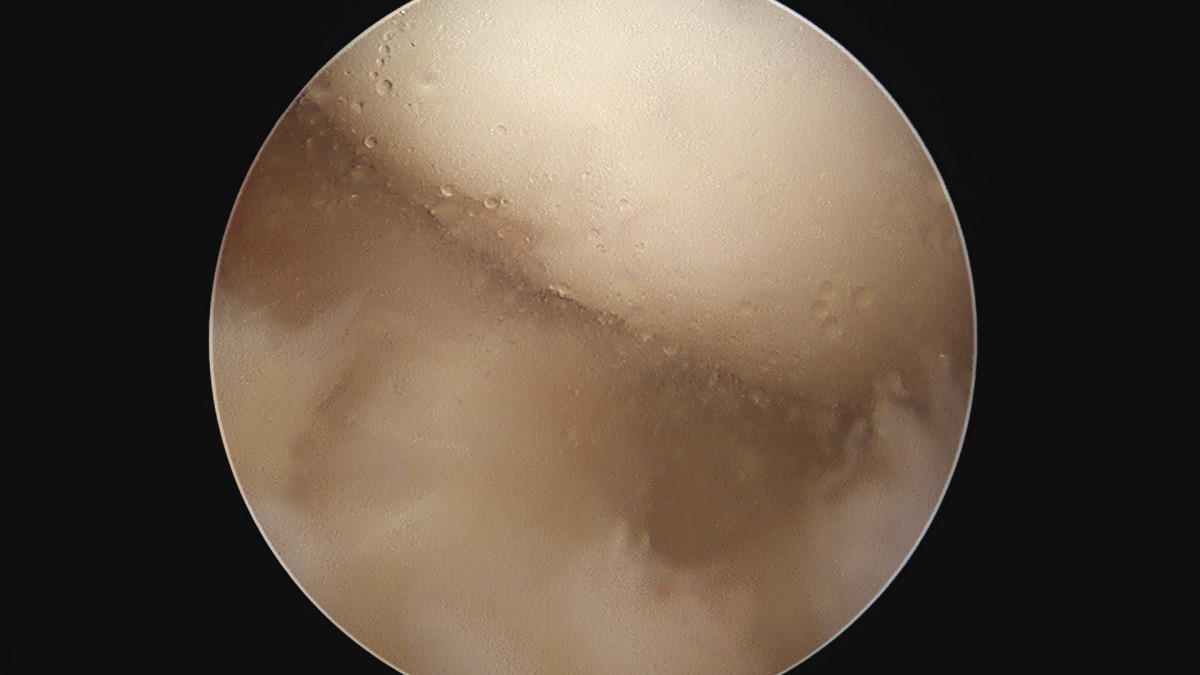

이재상원장님 무릎 반월상 연골판 절제술 안경O 환자

dae765e4d9ac96aee867c9d6292d8784_1758005875_2013.jpg